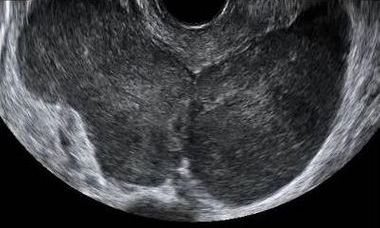

The January issue of Ultrasound in Obstetrics & Gynecology includes a meta-analysis evaluating the use of transvaginal ultrasound for diagnosing parametrial involvement in deep pelvic endometriosis, a retrospective study comparing the use of intertwin estimated fetal weight discordance vs singleton and twin fetal growth charts for predicting adverse perinatal outcomes in twins, a paper assessing the effectiveness of the first-trimester anomaly scan, and a prospective study examining the efficacy of a multimodal sonographic approach compared with transvaginal ultrasound for endometrial assessment in abnormal uterine bleeding.